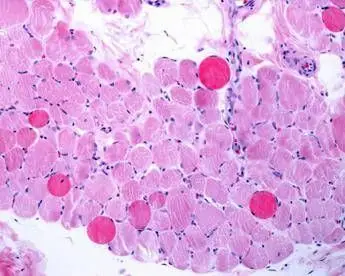

Malattie rare, risultati positivi a 5 anni per vamorolone in distrofia Duchenne

(Adnkronos) - 'Migliore profilo di sicurezza con efficacia paragonabile a quella dei corticosteroidi standard'